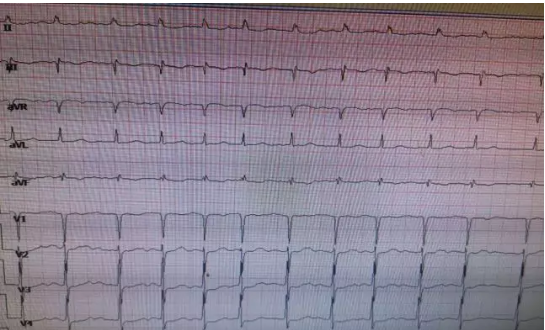

微信截图_20210615082207.png

图1、阵发性室上性心动过速心电图